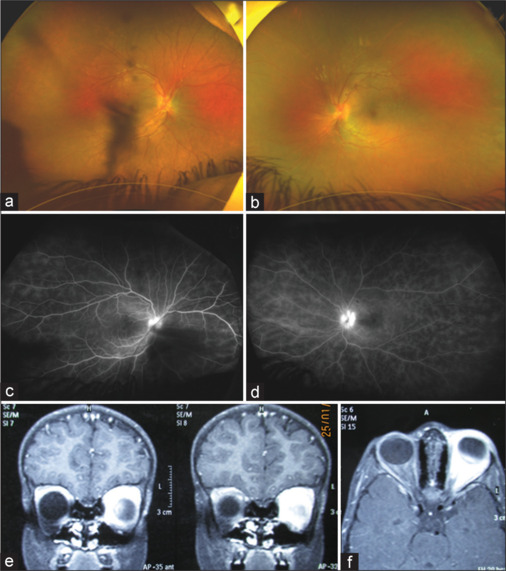

一例年轻女孩的全葡萄膜炎伴突出。

A curious case of Panuveitis with proptosis in a young girl.